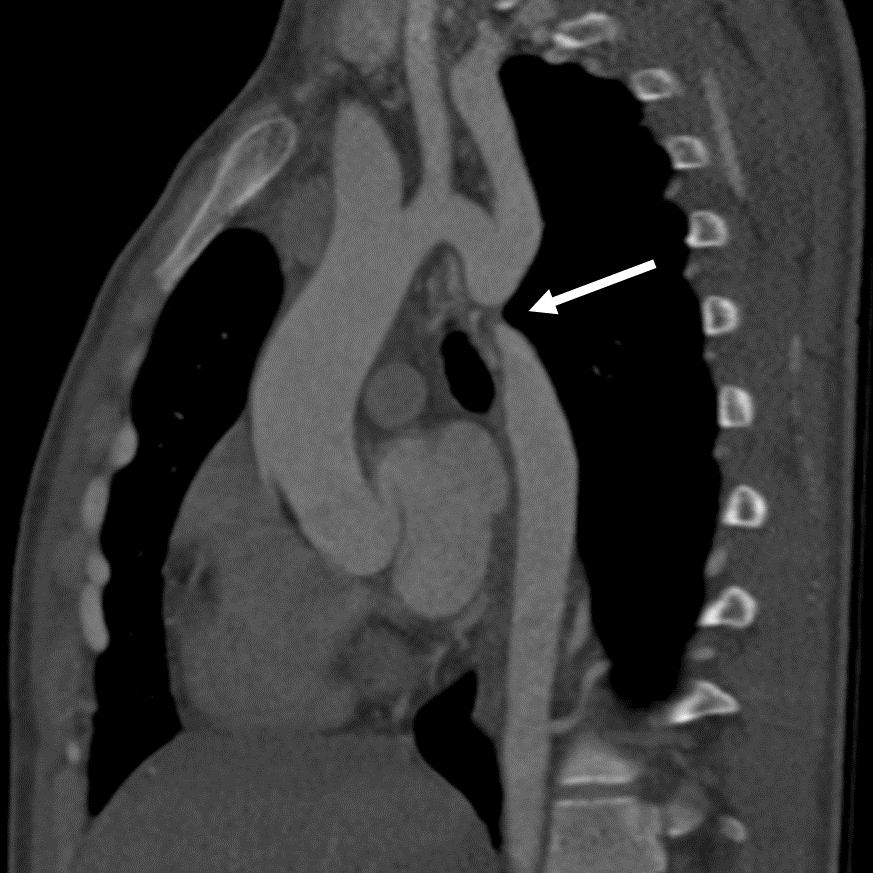

术后复查

患者术后6个月复查CTA显示支架位置理想,且无并发症。

术后CTA影像